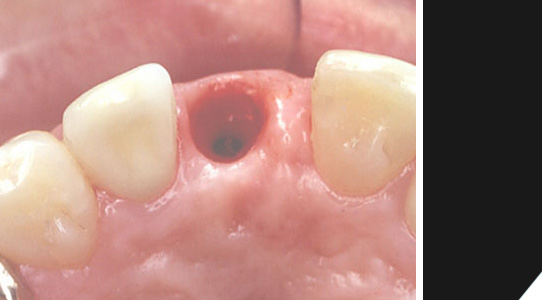

Das Implantat wurde anstelle der Wurzel in den Knochen eingebracht. Ein Zahnfleischformer bereitet die Lücke für die prothetische Versorgung vor. In dieser Phase kann man bereits von einer Übergangslösung sprechen.